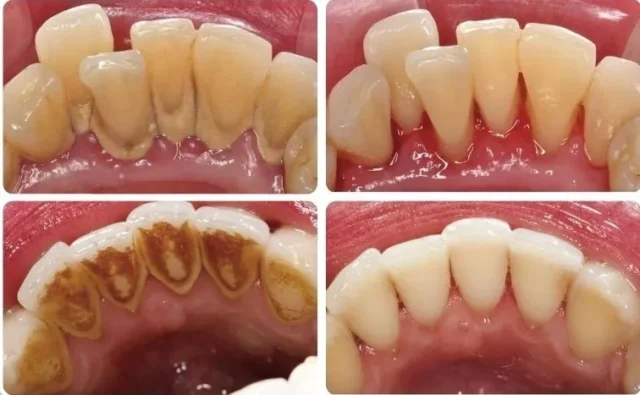

Mảng bám vi khuẩn là lớp kem dính, mềm, liên tục hình thành trên bề mặt răng, đặc biệt là ở các vùng khó vệ sinh như giữa các răng, dưới đường viền nướu. Nếu không được loại bỏ đúng cách, mảng bám này sẽ trở thành cao răng cứng chắc, bám chặt vào răng, gây kích ứng, viêm nhiễm và phá hủy mô nướu.

Cao răng không chỉ là nguyên nhân trực tiếp gây viêm nướu mà còn tạo điều kiện thuận lợi cho vi khuẩn phát triển, làm trầm trọng thêm tình trạng viêm nhiễm. Quan trọng nhất, việc chủ quan vệ sinh răng miệng kém sẽ thúc đẩy tốc độ hình thành cao răng, dẫn đến quá trình viêm nhiễm kéo dài và khó kiểm soát hơn.